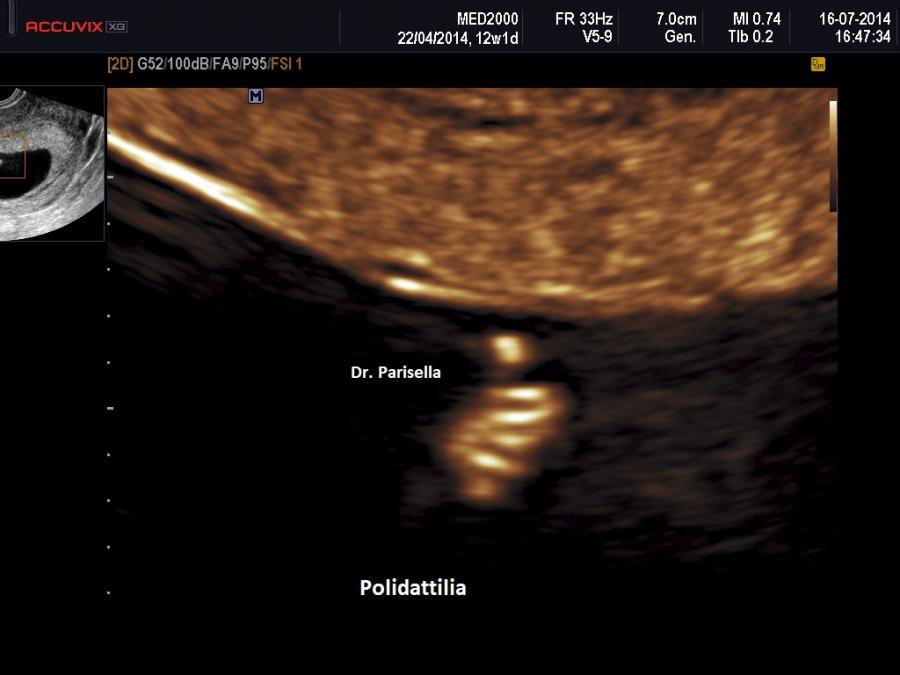

• Displasia scheletrica: ossa lunghe curve, agenesia della fibula, aspetto a ventaglio delle dita dei piedi, polidattilia;